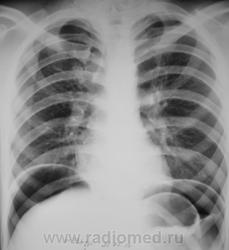

Да, на обзорге ОГК стенка свода желудка ровная, тонкая (париетография прям). А на РГ ОБП между газом слева и пузырем желудка какая-то тень, может кровь натекла?

А рана где? Может это внутристеночная гематома желудка (негомогенно смотрится). Однако же, коллеги, ну пофантазируйте: вот два снимка, на одном стенка свода линейная, на втором - нет. Что это (кроме занудного ответа "скиалогия":)